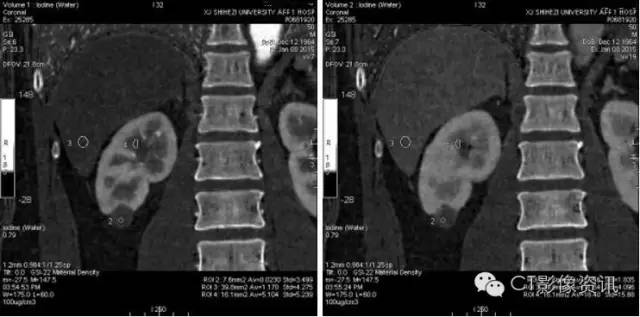

进行能谱分析,碘含量测量,三期病变内部碘含量相似,且接近0的水平,提示病变没有强化。

三期冠状位测量结果显示同样结果。肝实质、肾脏髓质均有明显强化。

最终诊断:肾囊肿。

讨论 能谱的功能可以解决临床中有争论或者诊断不明确的情况。尽管常规显示中似乎有强化的存在,但不能确切诊断。但该病例通过碘含量的测量,明确了病灶没有强化。为最终诊断定下根本的线索。